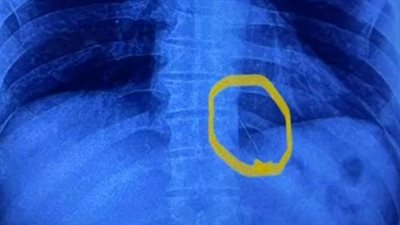

فريق طبي ينجح في استخراج إبرة تنجيد استقرت بصدر مريض منذ عامين بـ القليوبية | بث مباشر

الخميس 06/10/2022 05:20 م